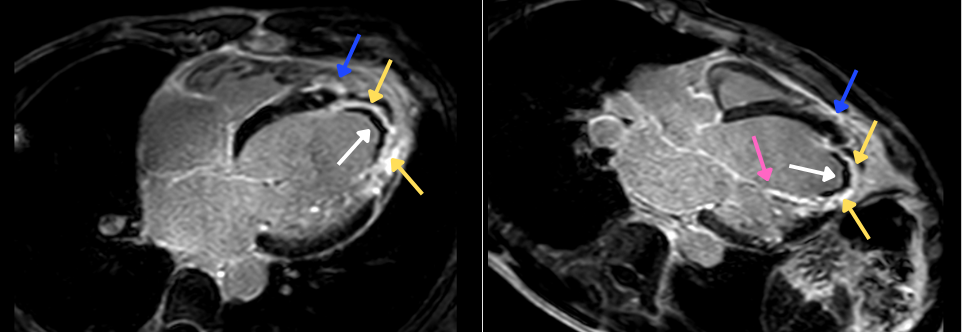

First-pass perfusion and Cine SSFP sequences. Large apical filling defect - white arrows. Apical mural thrombus - red arrows.